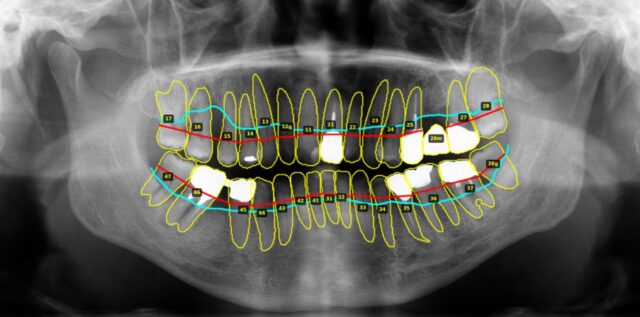

私はこの課題に対して、開発しているパノラマエックス線画像AIを核に、歯科情報を「標準化」し「検索可能」にすることで、警察歯科(事件・身元不明遺体)や大規模災害(将来の南海トラフ等)での個体識別を、より迅速・確実にする仕組みづくりができると考えております。

パノラマエックス線画像には、

- 歯科疾患(う蝕、根尖病変等)

- 歯式(現在歯・欠損歯・補綴の状況)

- 歯槽骨の状態(歯周病の状態)

といった個人差が反映されやすい顎顔面領域の多くの情報が1枚に含まれています。

これらの情報を組み合わせると、個体識別に耐えうる“歯科データ”になります。

↑歯式AI

↑歯周病AI

①歯科治療、②カルテ入力(P病名等)、③歯科健診(スクリーニング)、④お口年齢、⑤公衆衛生・疫学調査、⑥個体識別・身元確認などに幅広く活用できる客観的データです。

個体識別において特に重要なのが、「歯式AI」による識別項目です。

私は少なくとも次のような要素を“構造化データ”に落とし込むことが可能です。

- 現在歯(治療の有無は問わない)

- インプラント

- 欠損歯

- ポンティック(ブリッジの欠損部)